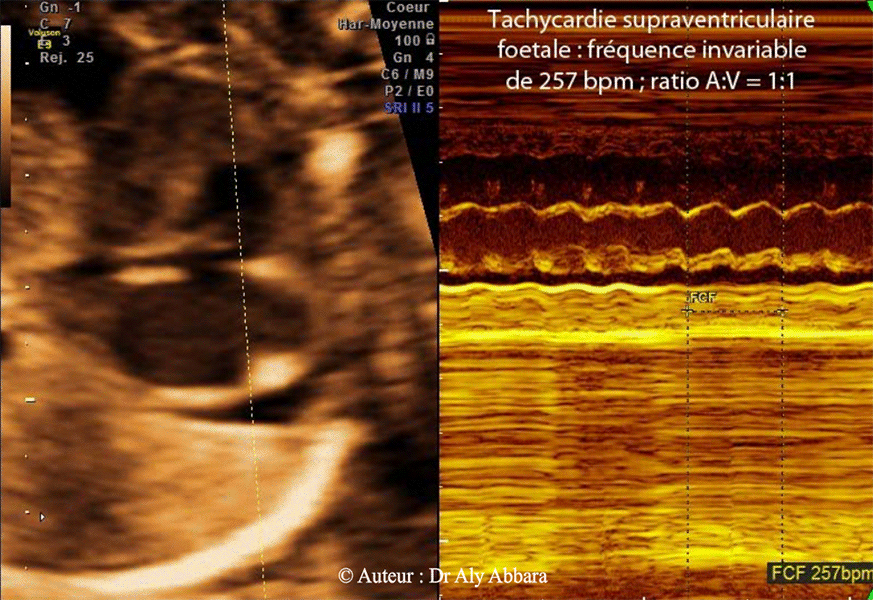

Tachycardie supra ventriculaire avec normalisation du rythme cardiaque foetal spontanément au bout de 20 minutes

• Images échographiques en mode-M montrant la présence d'une anomalie du rythme cardiaque fœtal sous forme de tachycardie supraventriculaire intermittente : oreillettes et ventricules cardiaques battant à une fréquence très élevée et invariable de 257 battements par minute (bpm) ; le ratio A:V (fréquence auriculaire/fréquence ventriculaire) est égale à "1", donc absence de bloc auriculo-ventriculaire.

• Cette tachycardie supraventriculaire fœtale est intermittente : des périodes de tachycardie durant de 15 à 20 minutes séparées par des intervalles du rythme cardiaque sinusal normal (145 à 160 bpm) durant 20 à 25 minutes, voire parfois plus.

• Cette anomalie du rythme cardiaque fœtal a été mise en évidence au terme de 23 SA, chez un fœtus présentant des signes échographiques d'anasarque fœto-placentaire : épanchement péricardique ; ascite , hépato-splénomégalie et épaississement du placenta.

• L'étude de la morphologie générale et aussi cardiaque fœtale ne montre pas d'anomalie particulière en dehors de la présence de signes pouvant être attribuées à l'insuffisance cardiaque fœtale : cardiomégalie et hypertrophie des deux oreillettes.

• L'insuffisance cardiaque compliquée par l'anasarque fœtoplacentaire peut être la conséquence de la présence de cette tachycardie supraventriculaire fœtale intermittente.